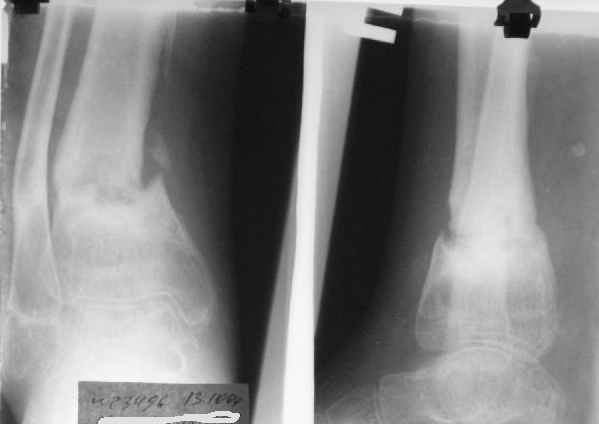

Формирование некроза кожи по задней поверхности н\3 голени~ 1 %, вторичное заживление, кожная пластика. Нейропатия м\берцового нерва (отсутствие активного разгибания 1 пальца) На вытяжении около 8 нед, в дальнейшем в гипсовых повязках ~ 8 мес.

В январе 2005: варусная деформация н\3 голени, болевой с-м, комбинированная контрактура г\стопного сустава, нейропатия м\берцового нерва сохраняется слабость разгибания 1 пальца.

На данный момент ходит при помощи костыля (без присмотра -без костыля :), разрабатывает движения в г\стопном суставе.

AVM> А каково у него укорочение голени?

В пределах 2 см.

Не катастрофа. Рост продолжается, будем следить в динамике.

Промежуточный